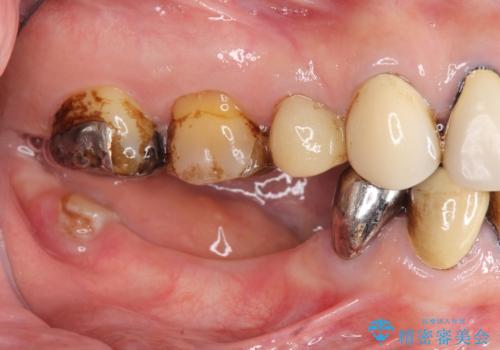

- インプラント治療を希望し数軒の医院で治療の相談をするも、骨の量が足りず治療が難しいと断られたのち当院にも相談にみえました。

長年の義歯の使用により骨の幅は非常に薄くインプラントを埋入するには大規模な骨の造成が必要な状態です。

また骨の問題だけでなく、完成後に歯ブラシがしやすいよう歯ぐきの移植も行いよりインプラント周囲の環境が安定するよう環境を整える治療計画を立てます。